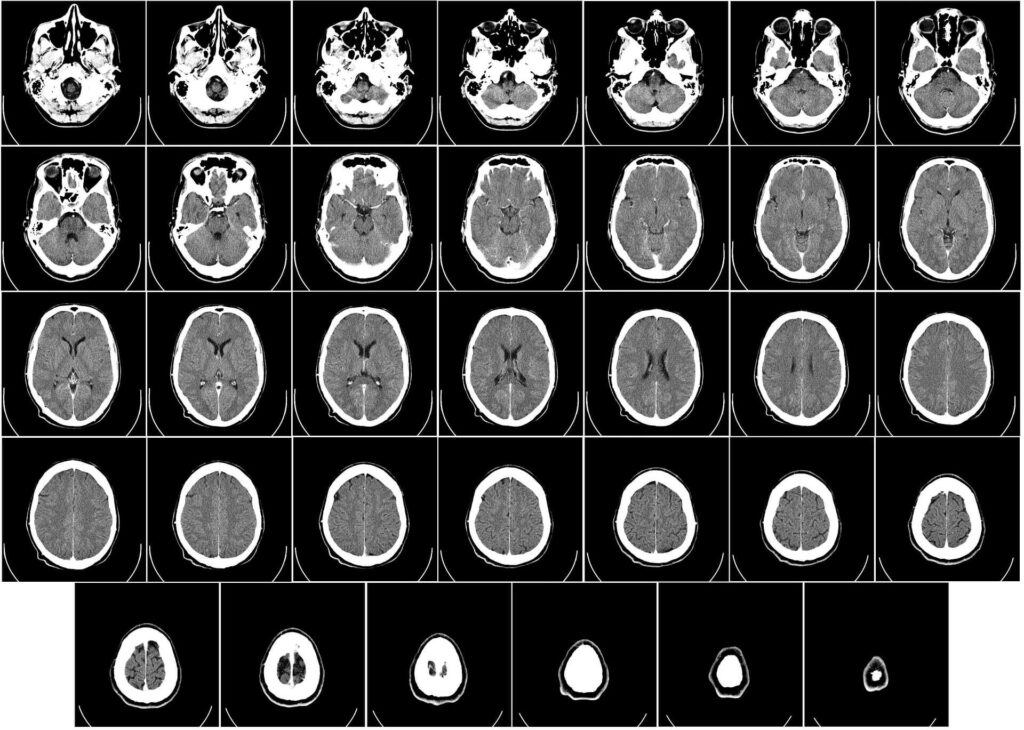

¿Qué impacto tienen los Algoritmos en Visión Artificial? Pues simplemente no existiría actualmente la imagen médica sin algoritmos que nos ayuden.

Juegan un papel fundamental al permitir el análisis y procesamiento de datos en formato imagen para extraer información visual. Existen diferentes tipos de algoritmos utilizados en la visión artificial, cada uno con su enfoque y aplicación específica.